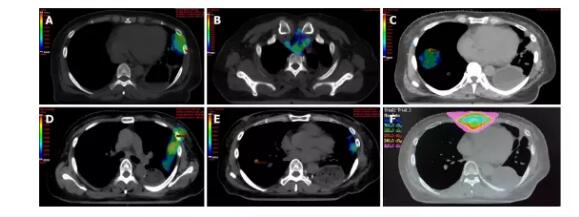

体检 该患者于2019年7月31日再次入院时,脸色苍白且脱水,身体左胸壁伤口重新张开,约2厘米×3厘米,并散发着恶臭化脓性分泌物。 实验室检查 2019年8月8日对胸膜引流液进行细菌培养和药物敏感性测试,结果显示耐甲氧西林的金黄色葡萄球菌和白色念珠菌呈阳性。定期对胸膜脓肿引流液进行细菌培养,表明存在铜绿假单胞菌(8月29日)和小肠克雷伯菌(9月30日)。 影像检查 当患者于2019年5月就诊时,全身正电子发射断层显像(PET-CT)显示形成了胃胸瘘,病变累及外侧胸壁(图3A和B),左肺活动性恶性肿瘤,下节段胸骨切开术,以及肝右叶。在内窥镜检查中确认到位于胃大曲率处的约5 cm的胃胸瘘(图3C和D)。2019年9月在计算机断层扫描(CT)检查中检测到所应用的引流管引流的脓肿不良。

然后患者接受2个月的充分引流并用三氧水冲洗。 结果与随访 病人的感染得到了令人满意的控制,胸腔闭式引流后白细胞数量和中性粒细胞比例逐渐降低(图4A和B)。降钙素原也下降,表明相关症状,包括严重的细菌感染和败血症,正在逐渐改善(图4C)。C反应蛋白水平波动,与患者潜在疾病的变化有关,包括阻塞性肺炎(图4D)。 治疗期间的CT检查显示,胃胸瘘壁逐渐增厚(图5A-F)。使用Interactive Medical Image Control System 21软件(比利时Materialise)从CT图像重建瘘管的三维立体图。使用ITK-SNAP 3.8.0(宾夕法尼亚大学的尤什科维奇和犹他大学的Gerig),基于瘘管的体素体积的总和来测量瘘管体积,分别为131、144、155、162、98和131。在8月20日,8月26日,8月30日,9月2日,9月17日和10月8日分别为96 mL(图5A’-F’)。